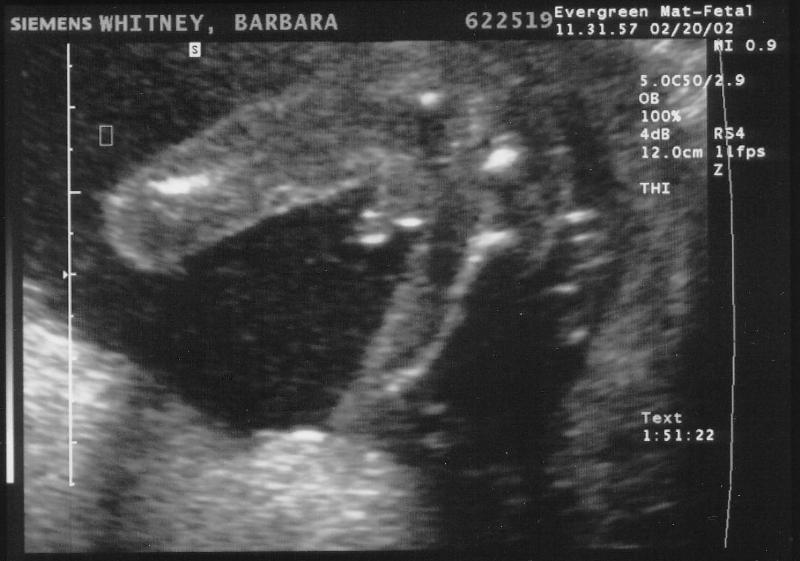

2002-02-20 11-31-57.jpg